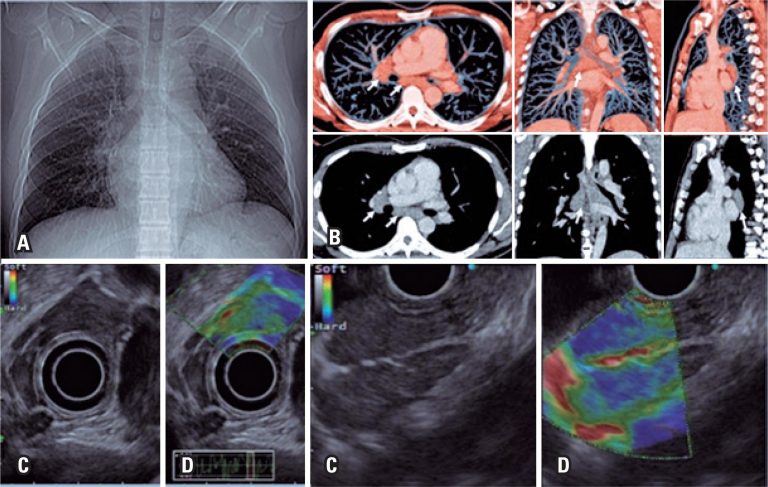

DOI: 10.31744/einstein_journal/2019MD5157

RESUMO A elastografia, procedimento difundido em ultrassonografia convencional, foi recentemente incorporada à ecoendoscopia. Trata-se de tecnologia inovadora e promissora, que visa aumentar o valor preditivo negativo da ultrassonografia endoscópica e das punções aspirativas com agulha fina. É útil para o direcionamento das punções em áreas suspeitas e, consequentemente, melhora o rendimento diagnóstico. Trata-se de técnica não invasiva, de fácil realização, sem custos adicionais ou complicações. As principais indicações são para análise de massas pancreáticas sólidas, linfonodos, lesões subepiteliais, lesões em […]

Palavras-chave: Aspiração por agulha fina guiada por ultrassom endoscópico/métodos; Biópsia por agulha fina; Broncoscopia; Linfonodos; Mediastino; Ultrassonografia de intervenção